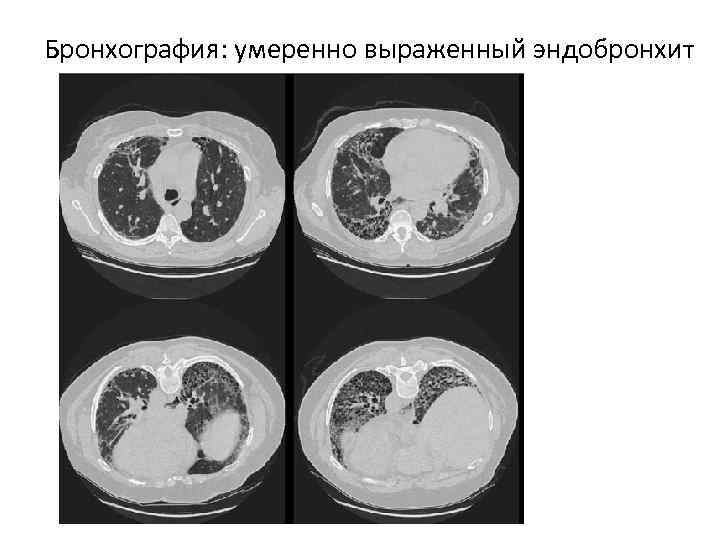

Бронхография: умеренно выраженный эндобронхит